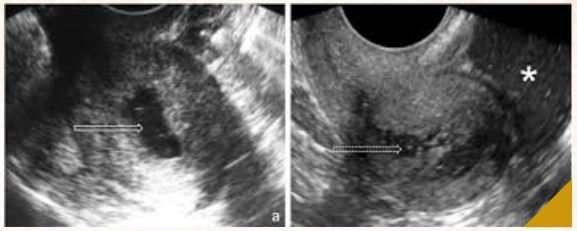

45a, G3PC2A1 Fluxo menstrual aumentado ha 3 anos Dismenorreia moderada 1. Atendimento 2. Exames solicitados 3. HD 4. Condutas

Apresentar-se (nome e funcao) 1. Nome, procedencia, religiao, estado civil, profissao QP, OPQRST Dor ciclica x nao-ciclica Caracteristicas do fluxo menstrual atual e previo Dismenorreia, dispareunia, sinusorragia Sintomas anemicos DUM e paridade Menarca e sexarca Contracepcao atual e uso de preservativo HMP (medic, comorb, cx, alerg) Vicios: tabag, alcool, drogas 2. Solicitar EF geral (pedir permissao, lavar as maos) e SV EF ginecologico e especular USG 3. Adenomiose (miometrio heterogeneo) 4. Hemograma, RNM para confirmacao Prescrever ACO Piroxicam nas crises, max 5 dias Retorno para seguimento Linguagem acessivel